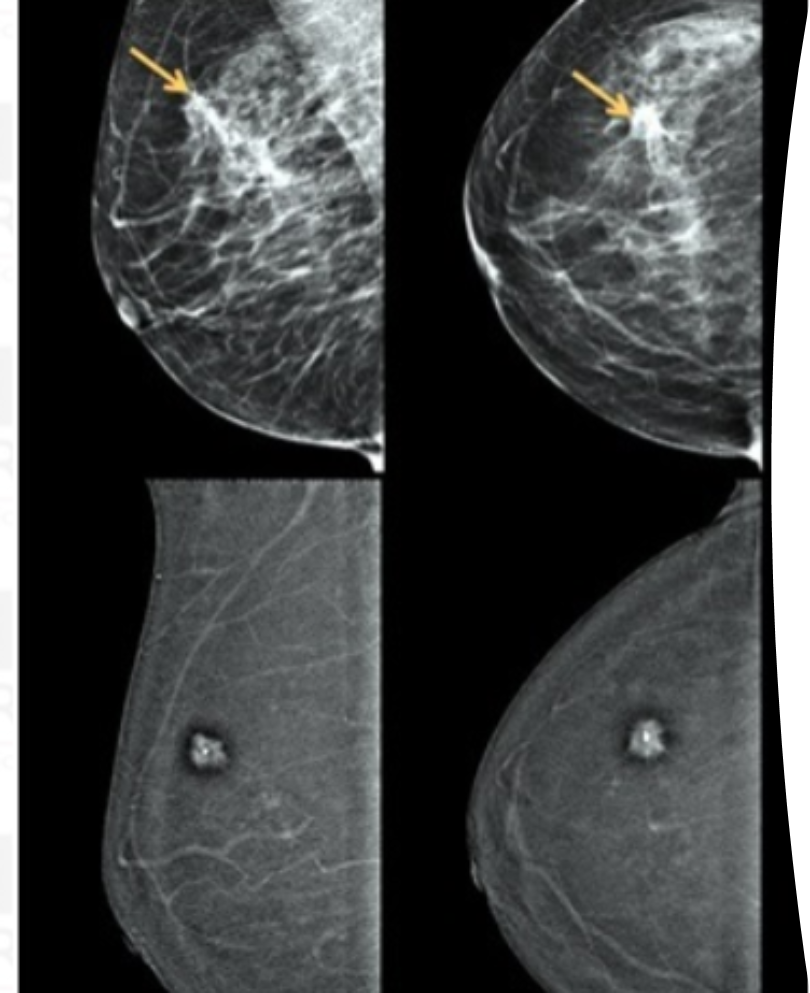

What is this image showing?

contrast enhanced mammography